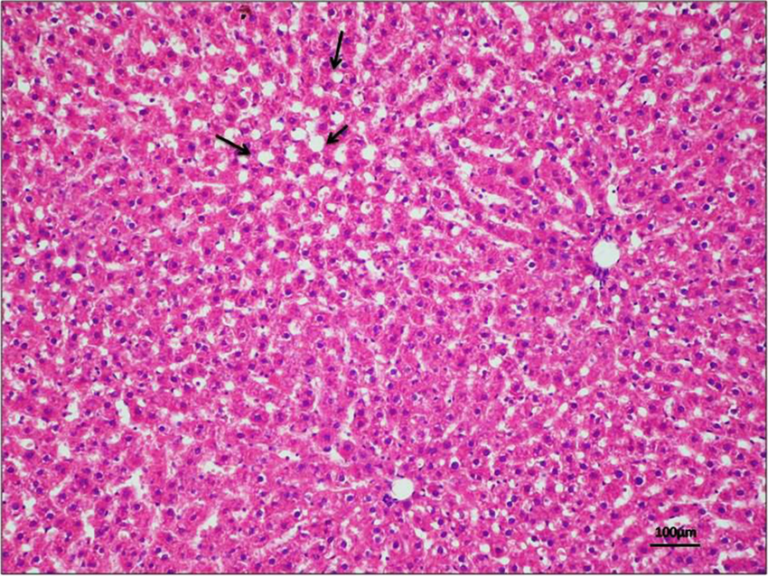

Liver Cells:

Actually, (I realized this after I made the labeled photos) in the top photo here, the white spot is NOT a central vein, because that photo is taken with higher magnification than the very first photo. The white spot is probably a smaller vein or one of the sinusoids labeled in the first picture.

liver cells found in my slides:

This is pretty blurry, but I think this is about the same magnification as the very first picture. This is the only one that I could find so far. I will keep looking.